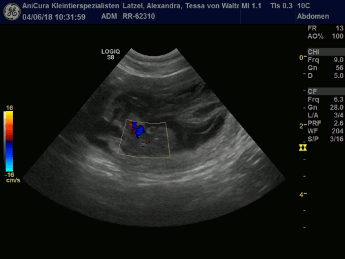

| 04.06.2018 |

Tessa und Uaine sind schwanger! Die Ultraschallbilder beweisen es! Hier die Bilder!!! |

| Dies sind die Ultraschallbilder von Tessa von Waltenweiler!!! |